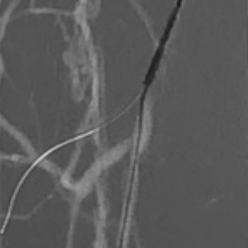

• Intra-luminal CTO crossing

• Heavily calcified in-stent restenosis

ONE CATHETER - MULTIPLE APPPLICATIONS